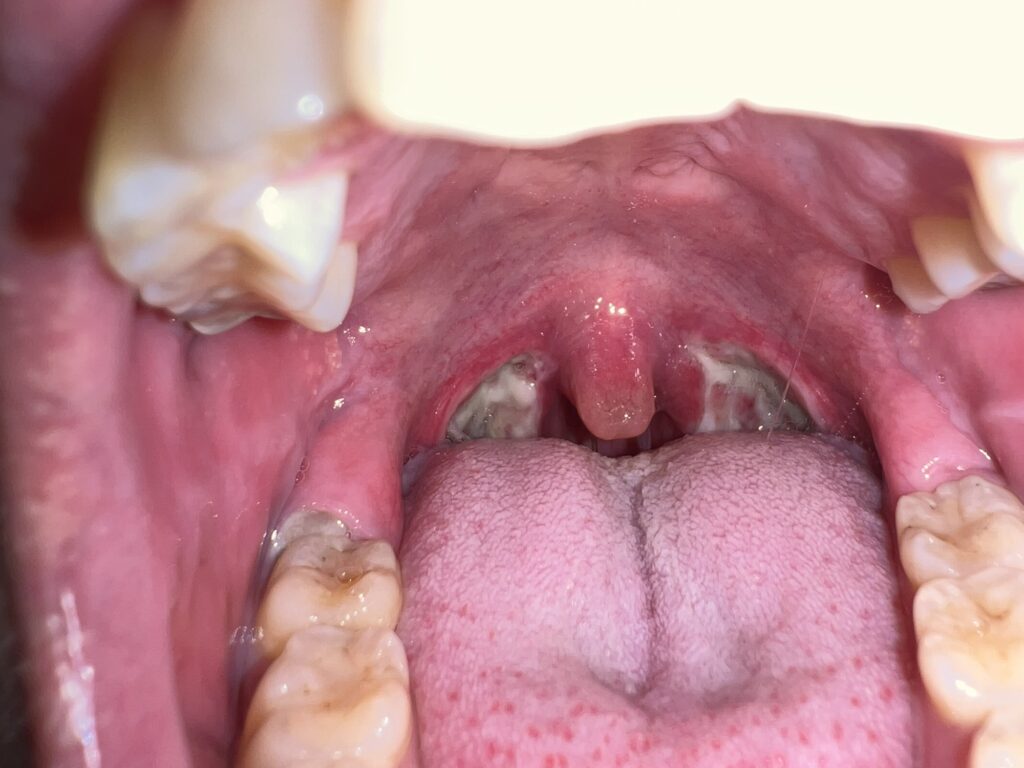

11月22日(退院日)

この白いものがポロポロ取れたら完治のようです。